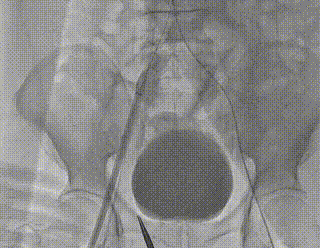

• 主入路:右股动脉(动脉超声引导穿刺,2把ProGlide预埋);

• 辅入路:左股动脉(动脉超声引导穿刺);

7.术后血管入路评估

主入路造影

双侧入路减影检查